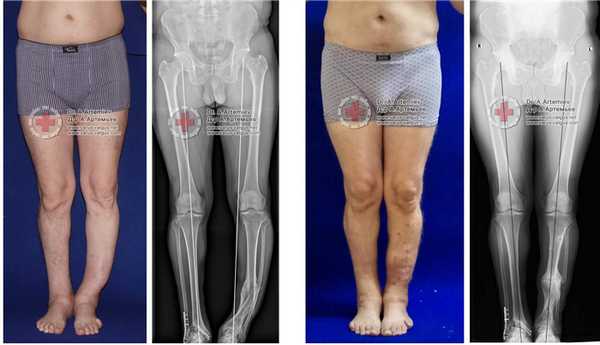

Эффект угловой коррекции при выраженном О-образном искривлении ног.

Слева - девушка 19 лет, справа - мужчина 26 лет.

Внешний вид и рентгенограммы девушки 19 лет с эстетически неблагоприятным распределением мягких тканей на голени до и после угловой коррекции и медиализации